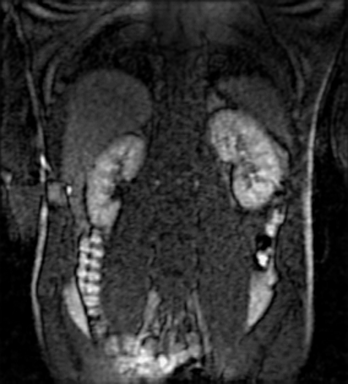

Tables 1 and 2 show our quantitative results: PSNR between the style (image we want to transfer style from) and generated image, SSIM and MS-SSIM between the content (image we want to take structure from) and generated image and finally, our proposed weighted SSIMs. For each style transfer direction and metric, our method consistently outperforms the other approaches. Figures 2 and 3 qualitatively highlight the good results of our method on 2D and 3D datasets. In addition, quantitative results on both figures show that our proposed metric preserves qualitative ordering of results for both style and content. In comparison, metrics such as SSIM struggle to accurately correlate to visual results.

Qualitative evaluation shows that the proposed method leads to sharper images, better content preservation, better localised CE and realistic MRI appearance. Quantitatively, we outperform the other algorithms with each metric, for each style transfer direction. While we expected that adding CE to images would be an easier task than removing CE, we found that for both tasks the method exhibits similarly performing quantitative and qualitative results. The results for style transfer with the kidney data show that when there is clear CE, it is easier to perform style transfer in both directions. However, when style transfer is performed on the prostate data, the model struggles in comparison to the kidney data. This may be due to the enhancement of the prostate being less defined than the kidney data. In figure 3(b), we can see the prostate with CE. Compared to figure 2(b) showing kidneys with CE, it is harder to determine the edges. The two original images shown in figures 3(a) and 3(b) are clear and easy to see some edges of prostate, in other images, it is harder to see the edges of the prostate.

(C) CW-SSIM: 0.92

(S) CW-SSIM: 0.59